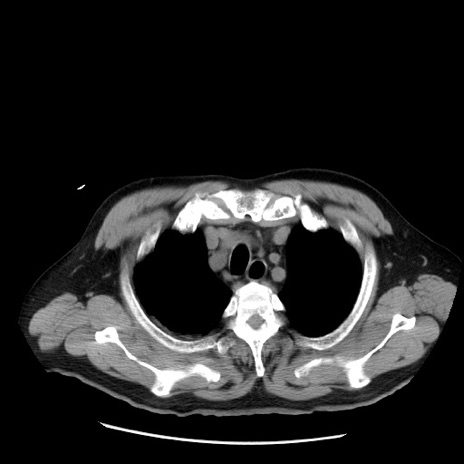

症例20(横断像)

【症例】 60歳代男性

【主訴】 腹部膨満、嘔吐

【現病歴】5日前頃より倦怠感を認め食事量減少し4日前の朝嘔吐、食事摂取困難となった。 3日前近医受診し点滴施行され整腸剤などを処方された。 当日他院を受診し、腹部膨満著明、炎症反応の上昇(CRP10.8、WBC11200)あり、紹介受診となる。

【身体所見】 意識JCS1 受け答えがはっきりしないBP 111/57mHg、 P 67bpm、、BT35.2°C、SpO2 97%(RA)、 腹部:膨隆、打診で鼓音あり、全体的に圧痛有り、腸蠕動音(-)、反跳痛ははっきりせず。

【データ】WBC 11400、CRP 14.20